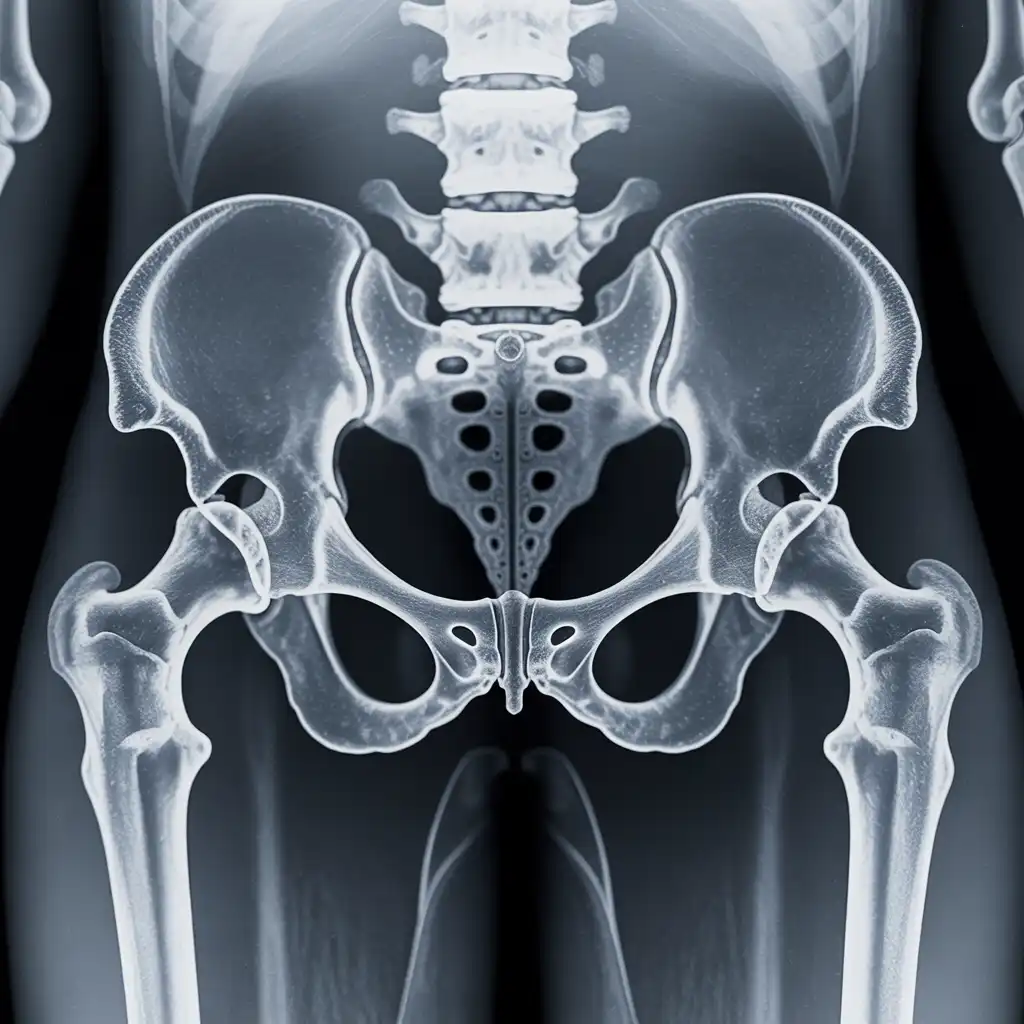

Il professionista entra con apparecchiature a basso dosaggio e schermi protettivi: bastano 2 × 2 m di spazio vicino al letto o alla poltrona. In pochi minuti acquisisce immagini HD, proprio come in un reparto ospedaliero.

Le immagini (formato DICOM) vengono caricate su un server crittografato e inviate immediatamente al radiologo. Se servono scatti aggiuntivi, il tecnico resta in collegamento video per eseguirli al volo.

Il medico radiologo analizza le immagini e firma il referto digitale all’istante. Ricevi il referto cartaceo e le immagini su chiavetta USB consegnati direttamente a casa tua subito dopo l'esame.

Usiamo le stesse apparecchiature certificate CE dei reparti ospedalieri, calibrate regolarmente. I referti sono validi per visite specialistiche, pronto soccorso e pratiche assicurative, e restano archiviati per 10 anni per ogni esigenza futura.